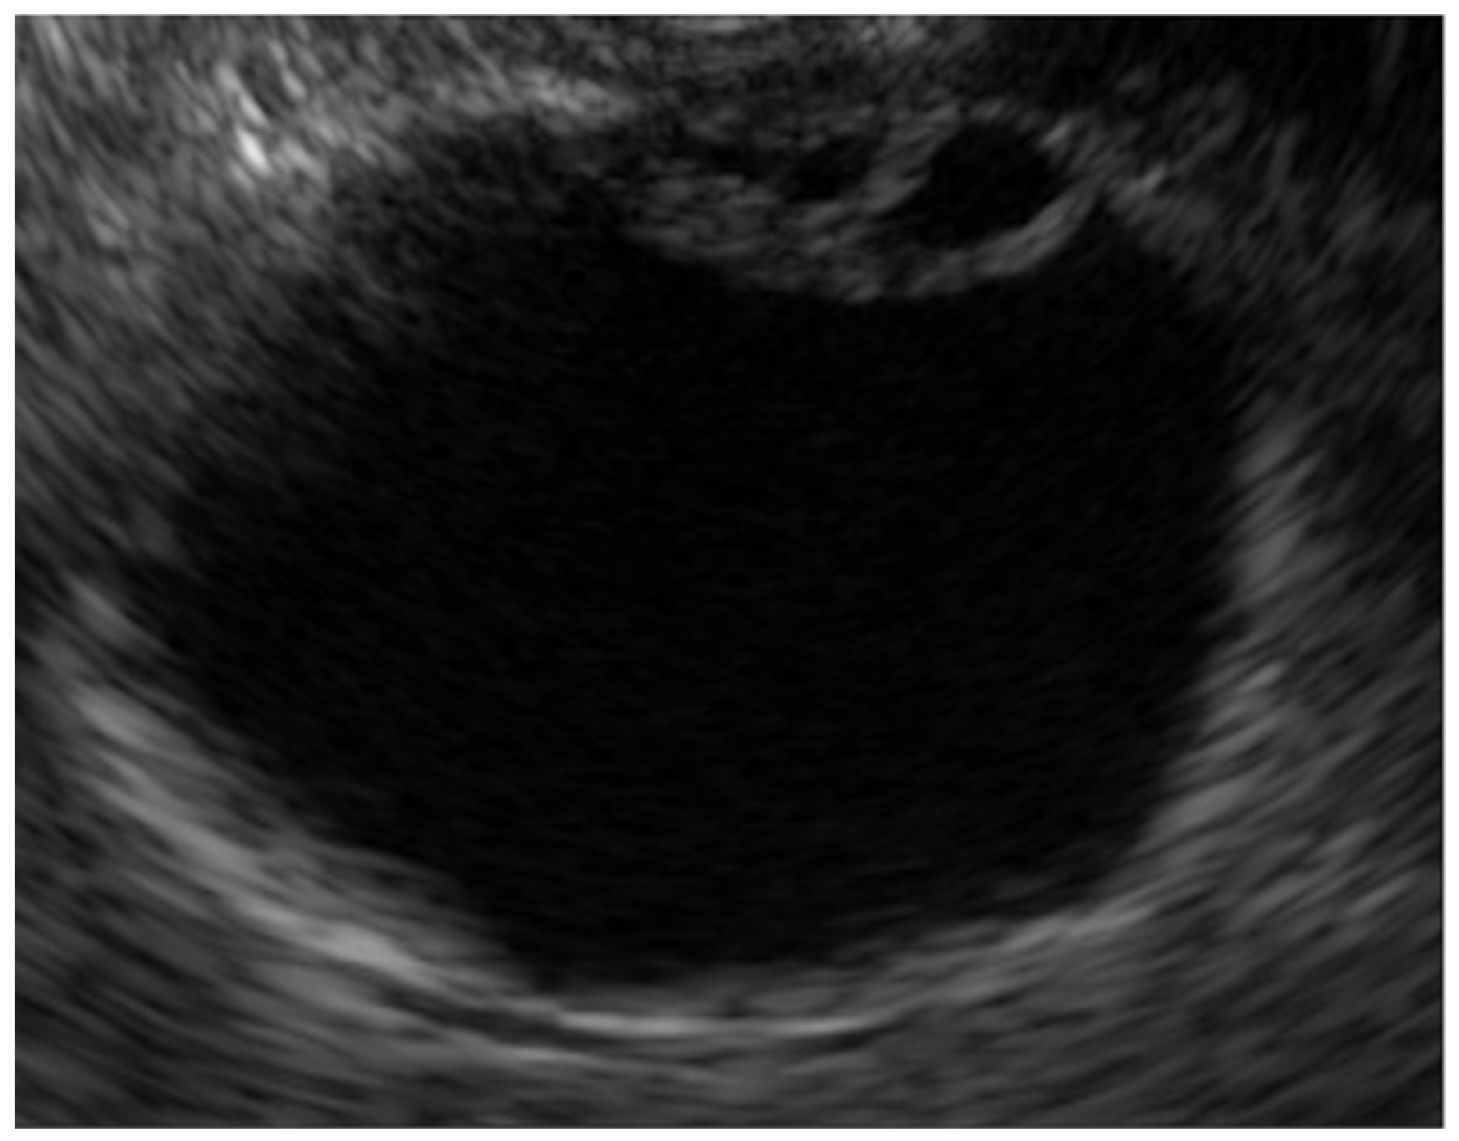

- Adenomyomatosis

| Adenomyomatosis | Smooth | Multiple anechoic areas comet tail artifact | Preserved |